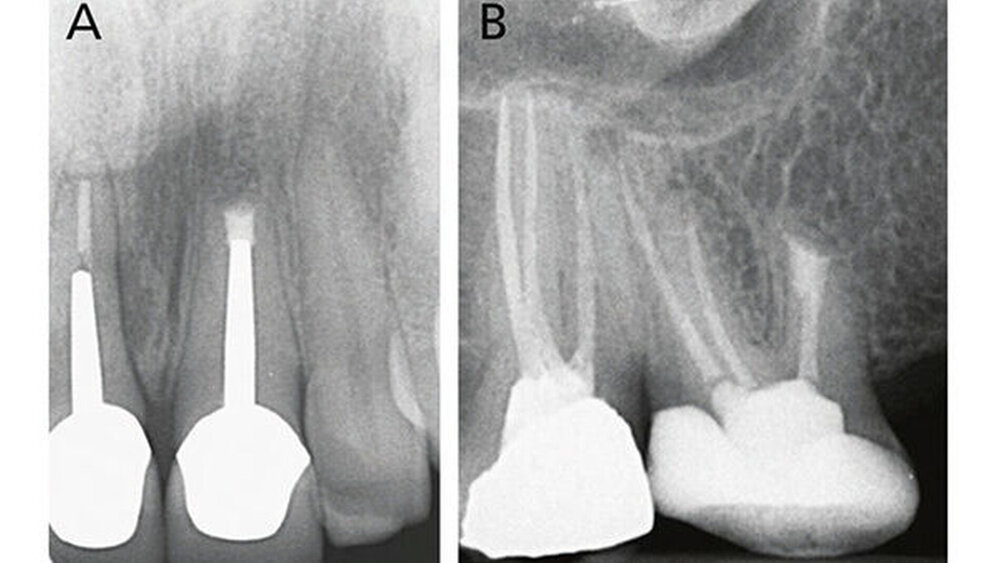

Klinische Studien

Die wesentlichen Daten von klinischen Studien über die Anwendung von MTA als retrogradem Füllmaterial sind in Tabelle III zusammengefasst. Die erste klinische Studie mit Auswertung der Erfolgsrate nach MTA-Anwendung in der apikalen Chirurgie wurde von Chong et al. (2003) publiziert - es war auch gleich die erste randomisierte Studie, welche MTA mit einem anderen retrograden Verschlusszement untersucht hat. Generell zeigen alle klinischen Studien sehr hohe Erfolgsraten für MTA in der apikalen Chirurgie (83,7% bis 96%). Die von uns 2014 publizierten Langzeitdaten (5 Jahre Beobachtungsdauer für alle behandelten Zähne) mit einer Erfolgsrate von 92,5% deuten auf eine sehr gute Stabilität und auf ein hohes Abdichtungsvermögen von MTA (von Arx et al. 2014) (Abb. 4 und 5).

Die Dokumentation der 10-Jahresdaten ist im Gange, und die bisherige Analyse deutet auf eine konstant hohe Erfolgsrate auch nach zehn Jahren (Abb. 6). Eine systematische Auswertung mit Meta-Analyse aller bis 2007 publizierten retrograden Füllmaterialien in Vergleichsstudien mit mindestens zwei getesteten Verschlussmaterialien ergab für MTA die höchste Wahrscheinlichkeit einer periapikalen Ausheilung (91,4%) (von Arx et al. 2010a).